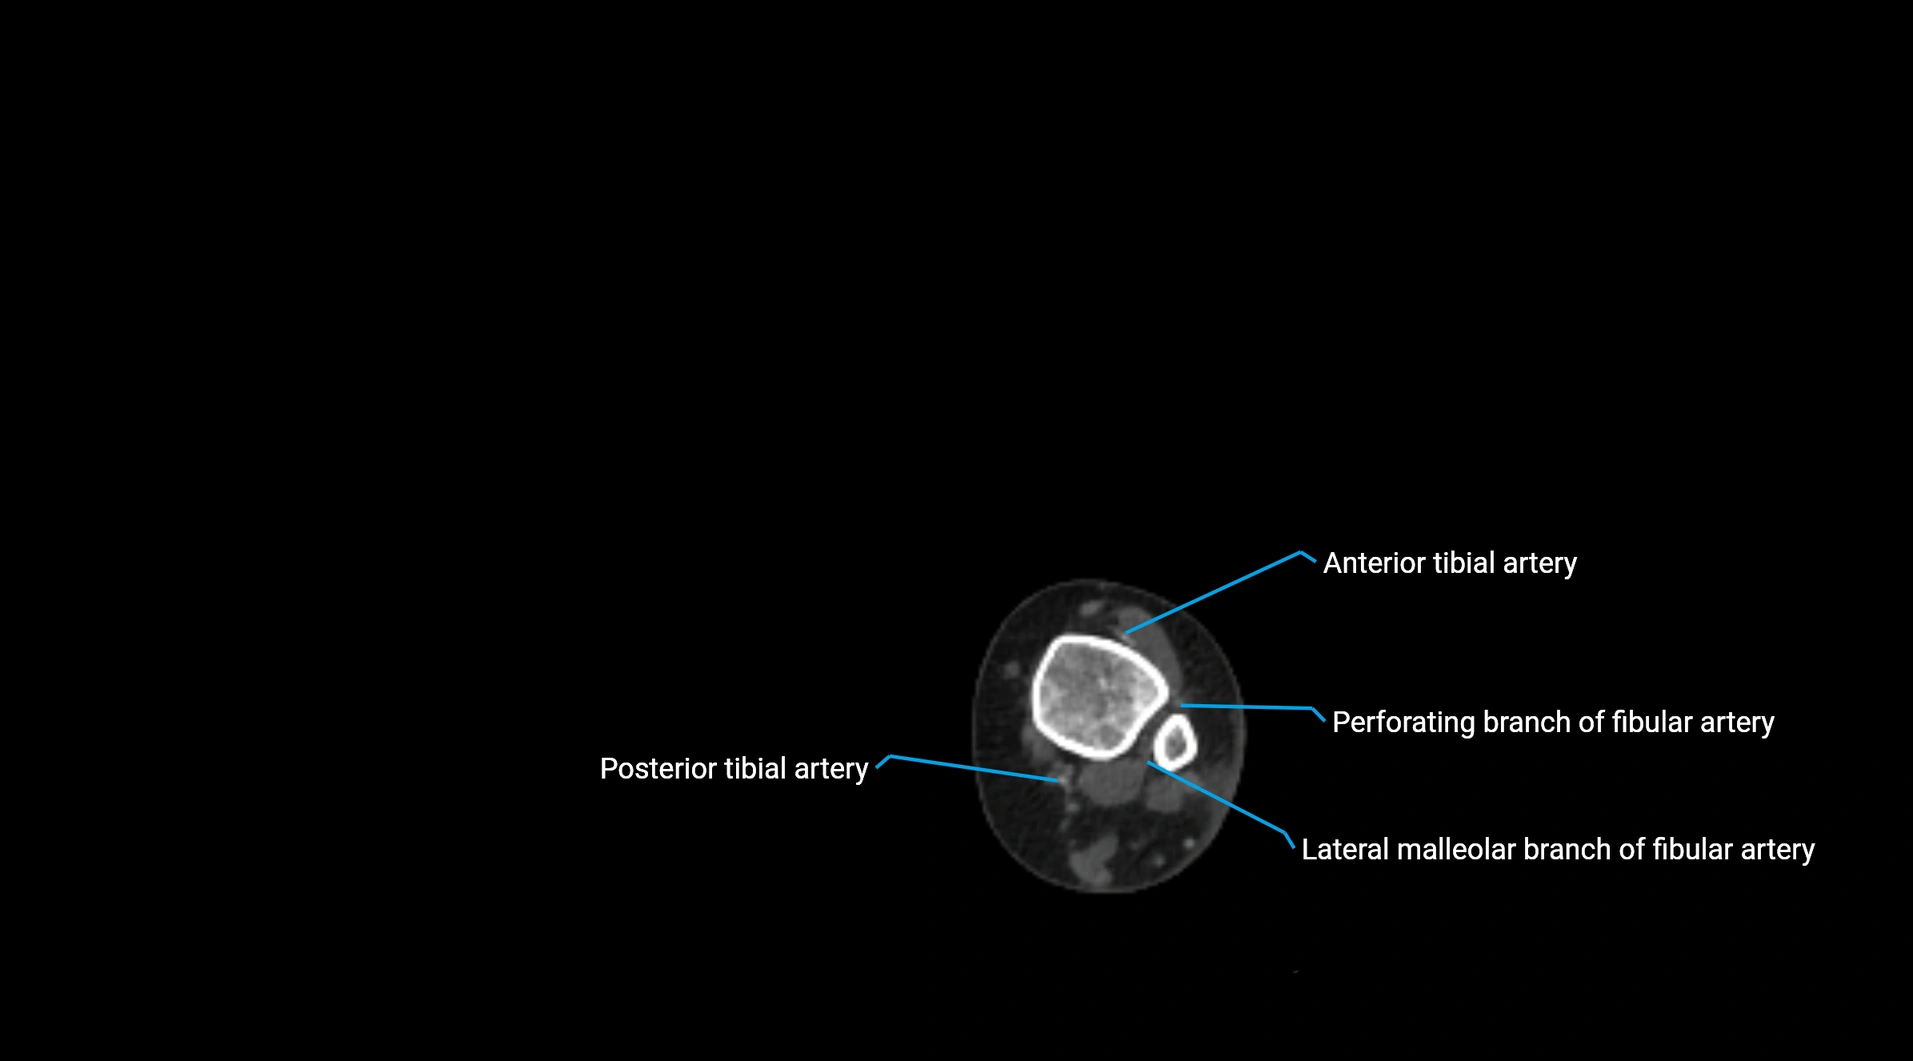

CT images

image

Contrast-enhanced CT (CTA):

• Gold standard for abdominal aortic imaging

• Provides excellent detail of lumen, wall, aneurysm, thrombus, and branch vessels

• Multiplanar and 3D reconstructions help in aneurysm measurement, stent graft planning, and dissection evaluation